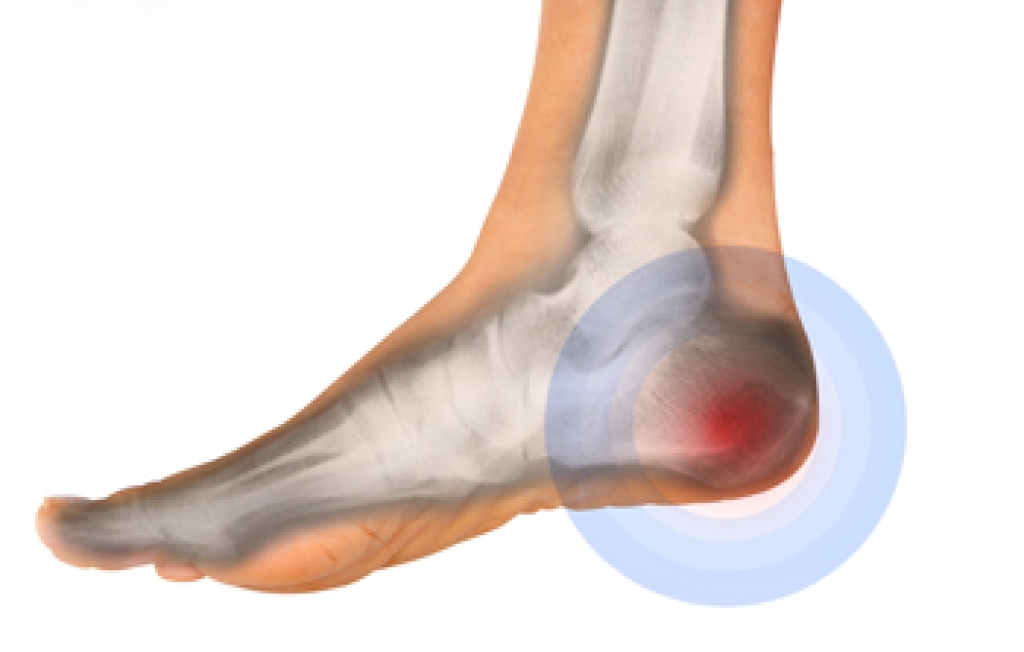

The Achilles tendon is a tendon that connects the lower leg muscles and calf to the heel of the foot. It is the strongest tendon in the human body and is essential for making movement possible. Because this tendon is such an integral part of the body, any injuries to it can create immense difficulties and should immediately be presented to a doctor.

There are various types of injuries that can affect the Achilles tendon. The two most common injuries are Achilles tendinitis and ruptures of the tendon.

Achilles Tendinitis Symptoms

- Inflammation

- Dull to severe pain

- Increased blood flow to the tendon

- Thickening of the tendon